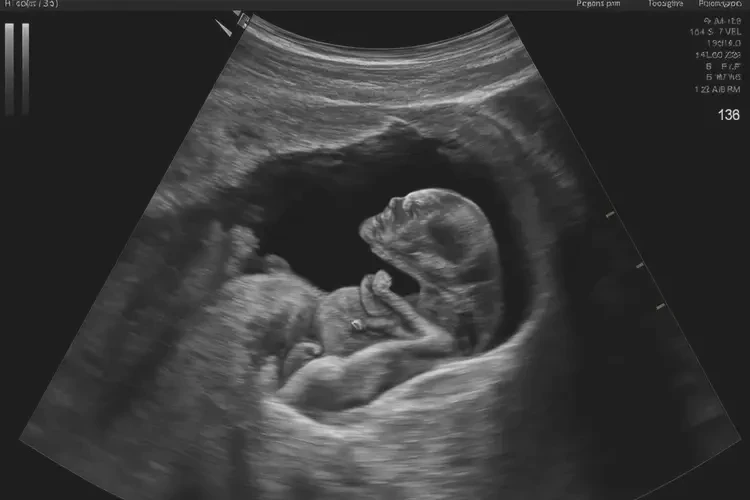

怀孕第37周,胎儿的胎心在136次/分钟是正常的。胎心率是指胎儿心脏每分钟跳动的次数,通常在120-160次/分钟之间被认为是正常的。在怀孕的不同阶段,胎心率可能会有所变化,但只要在正常范围内,就无需过于担心。

怀孕第37周胎心136次/分钟是正常的。如果发现胎心率异常,应及时就医,以便医生进行进一步的检查和处理。定期进行产前检查,监测胎心率和其他胎儿健康指标,对于确保胎儿的健康发育至关重要。